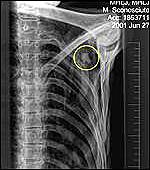

Recent advances in computerised tomography (CT), a sophisticated X-ray scan that allows multidimensional imaging, have given researchers an unprecedented view of Oetzi's internal anatomy. The pictures reveal a 13mm-long rip in Oetzi's left subclavian artery which lies just under the collar bone.

Blood poured out into the surrounding tissue, forming a hematoma that can be seen in the breast cavity.

"We can conclude that this was really a deadly hit from the arrowhead," said Dr. Frank Ruhli, University of Zurich. "He would not have walked around for days. It was a quick death.

"Theoretically, you could have been hit by an arrow and survive. If it doesn't hit an artery or the lung, and you don't get an infection it shouldn't be a problem."

Clotted blood also entered the hole caused by the arrow's wooden shaft, showing that it was broken off while Oetzi was still alive and therefore still bleeding. Dr Ruhli speculated that it was possible the Iceman removed the shaft himself. Alternatively, it could have been removed by an ally who tried in vain to help him, or perhaps by the attacker - if his arrows had a characteristic shaft - to try to cover up evidence linking him to the killing.

Officially, Oetzi climbed up to the Schnalstal Glacier and died from cardiac arrest, brought on by shock, after sustaining massive blood loss.